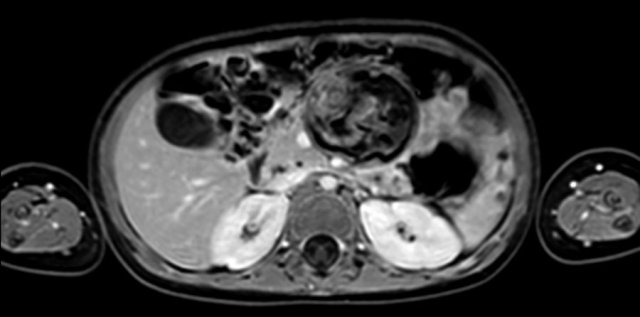

Same patient.

This is an axial gadolinium enhanced T1W-image with fat suppression.

It shows the encasement of the vessels.

Notice the tumor extension posterior to the aorta, which is displaced away from the vertebral column (arrow).

The extent of the tumor is well appreciated on a 3D axial T2 weighted TSE series.

The left kidney is compressed and displaced caudally.

Para-aortal lymph node metastases are present (small yellow arrow).

The origins of the celiac trunc and superior mesenteric artery are encased by tumor (arrowhead).

The inferior caval vein is lifted anteriorly (green arrow).

Bilateral dorsal atelectasis is often seen on the MRI, because the examination is done under anesthesia.